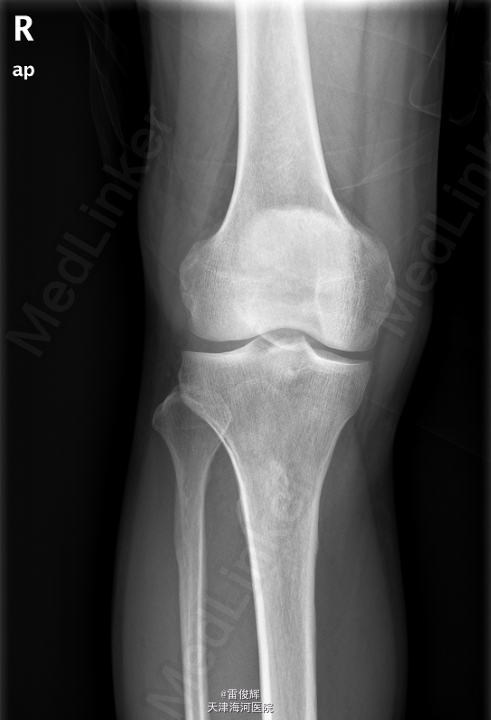

患者,男,46岁,因“外伤致右膝部肿痛伴活动受限3小时”入院。患者于3小时前不右左膝部撞击硬物后感剧烈疼痛,右膝部逐渐肿涨,活动受限,当即不能行走.

右膝关节肿胀明显,皮温不高,皮肤完整无破损,局部散在瘀斑,右膝关节活动受限,关节间隙及髌骨压痛(+),浮髌试验阴性. 本院X线片示:右髌骨骨折。